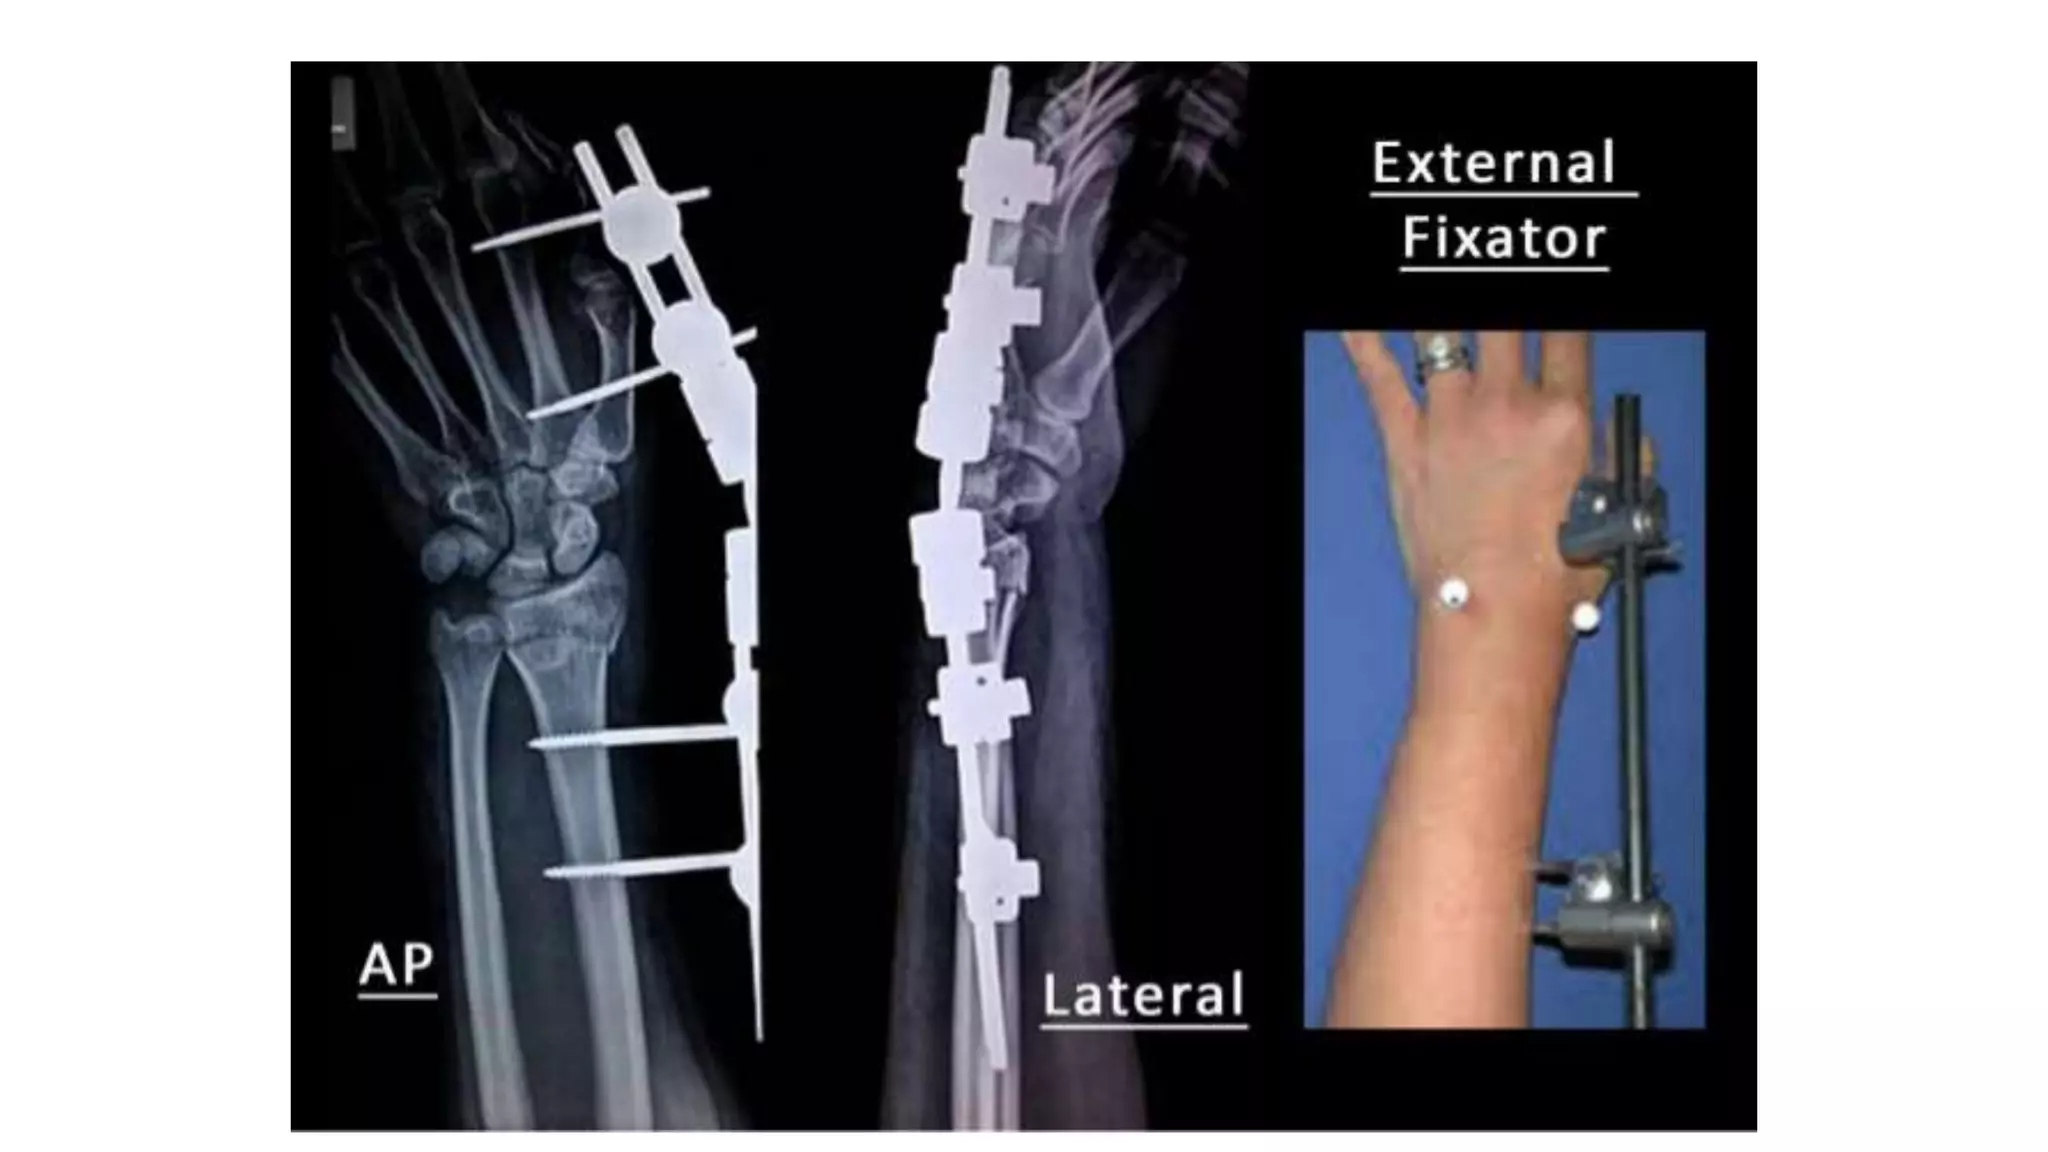

 But, if impaction is severe, even this

may not be enough to hold all the

fragments or maintain length.

 In that case, other techniques, such

as dorsal plating, locked intra-

medullary nails, external fixators,

internal plate bridging the radius to

the 3rd metacarpal & bone grafts

(Synthetic or autogenous) are

considered.

 But, ifimpaction is severe, even this may not be enough to hold all the fragments or maintain length.  In that case, other techniques, such as dorsal plating, locked intra- medullary nails, external fixators, internal plate bridging the radius to the 3rd metacarpal & bone grafts (Synthetic or autogenous) are considered.